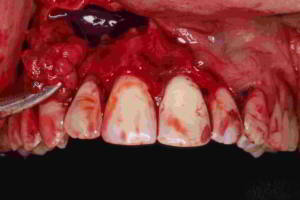

· Imagen 2, leer más...

La extirpación de la cápsula de un quiste recibe el nombre de quistectomía. Dicha intervención varía en función del tipo, localización y tamaño del mismo. Algunos pueden aparecer aislados (residuales), otros relacionados con algún diente erupcionado (radicular, periodontal lateral), con dientes no erupcionados (foliculares, paradentales) y algunos pueden ser unilobulados o bien multilobulados (botrioide). De cualquier forma, el tratamiento por lo general debe ser su extirpación completa.